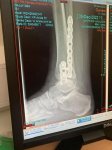

Thanks everyone! Appointment is at 10.40 so I’m up, showered and just had breakfast.

Feels like it’s been a long time, but also feels like it was just last week. Strange how time can feel so different. Looking forward to getting my leg back, but I hate that weird feeling when a cast comes off that your limb doesn’t belong to you ?